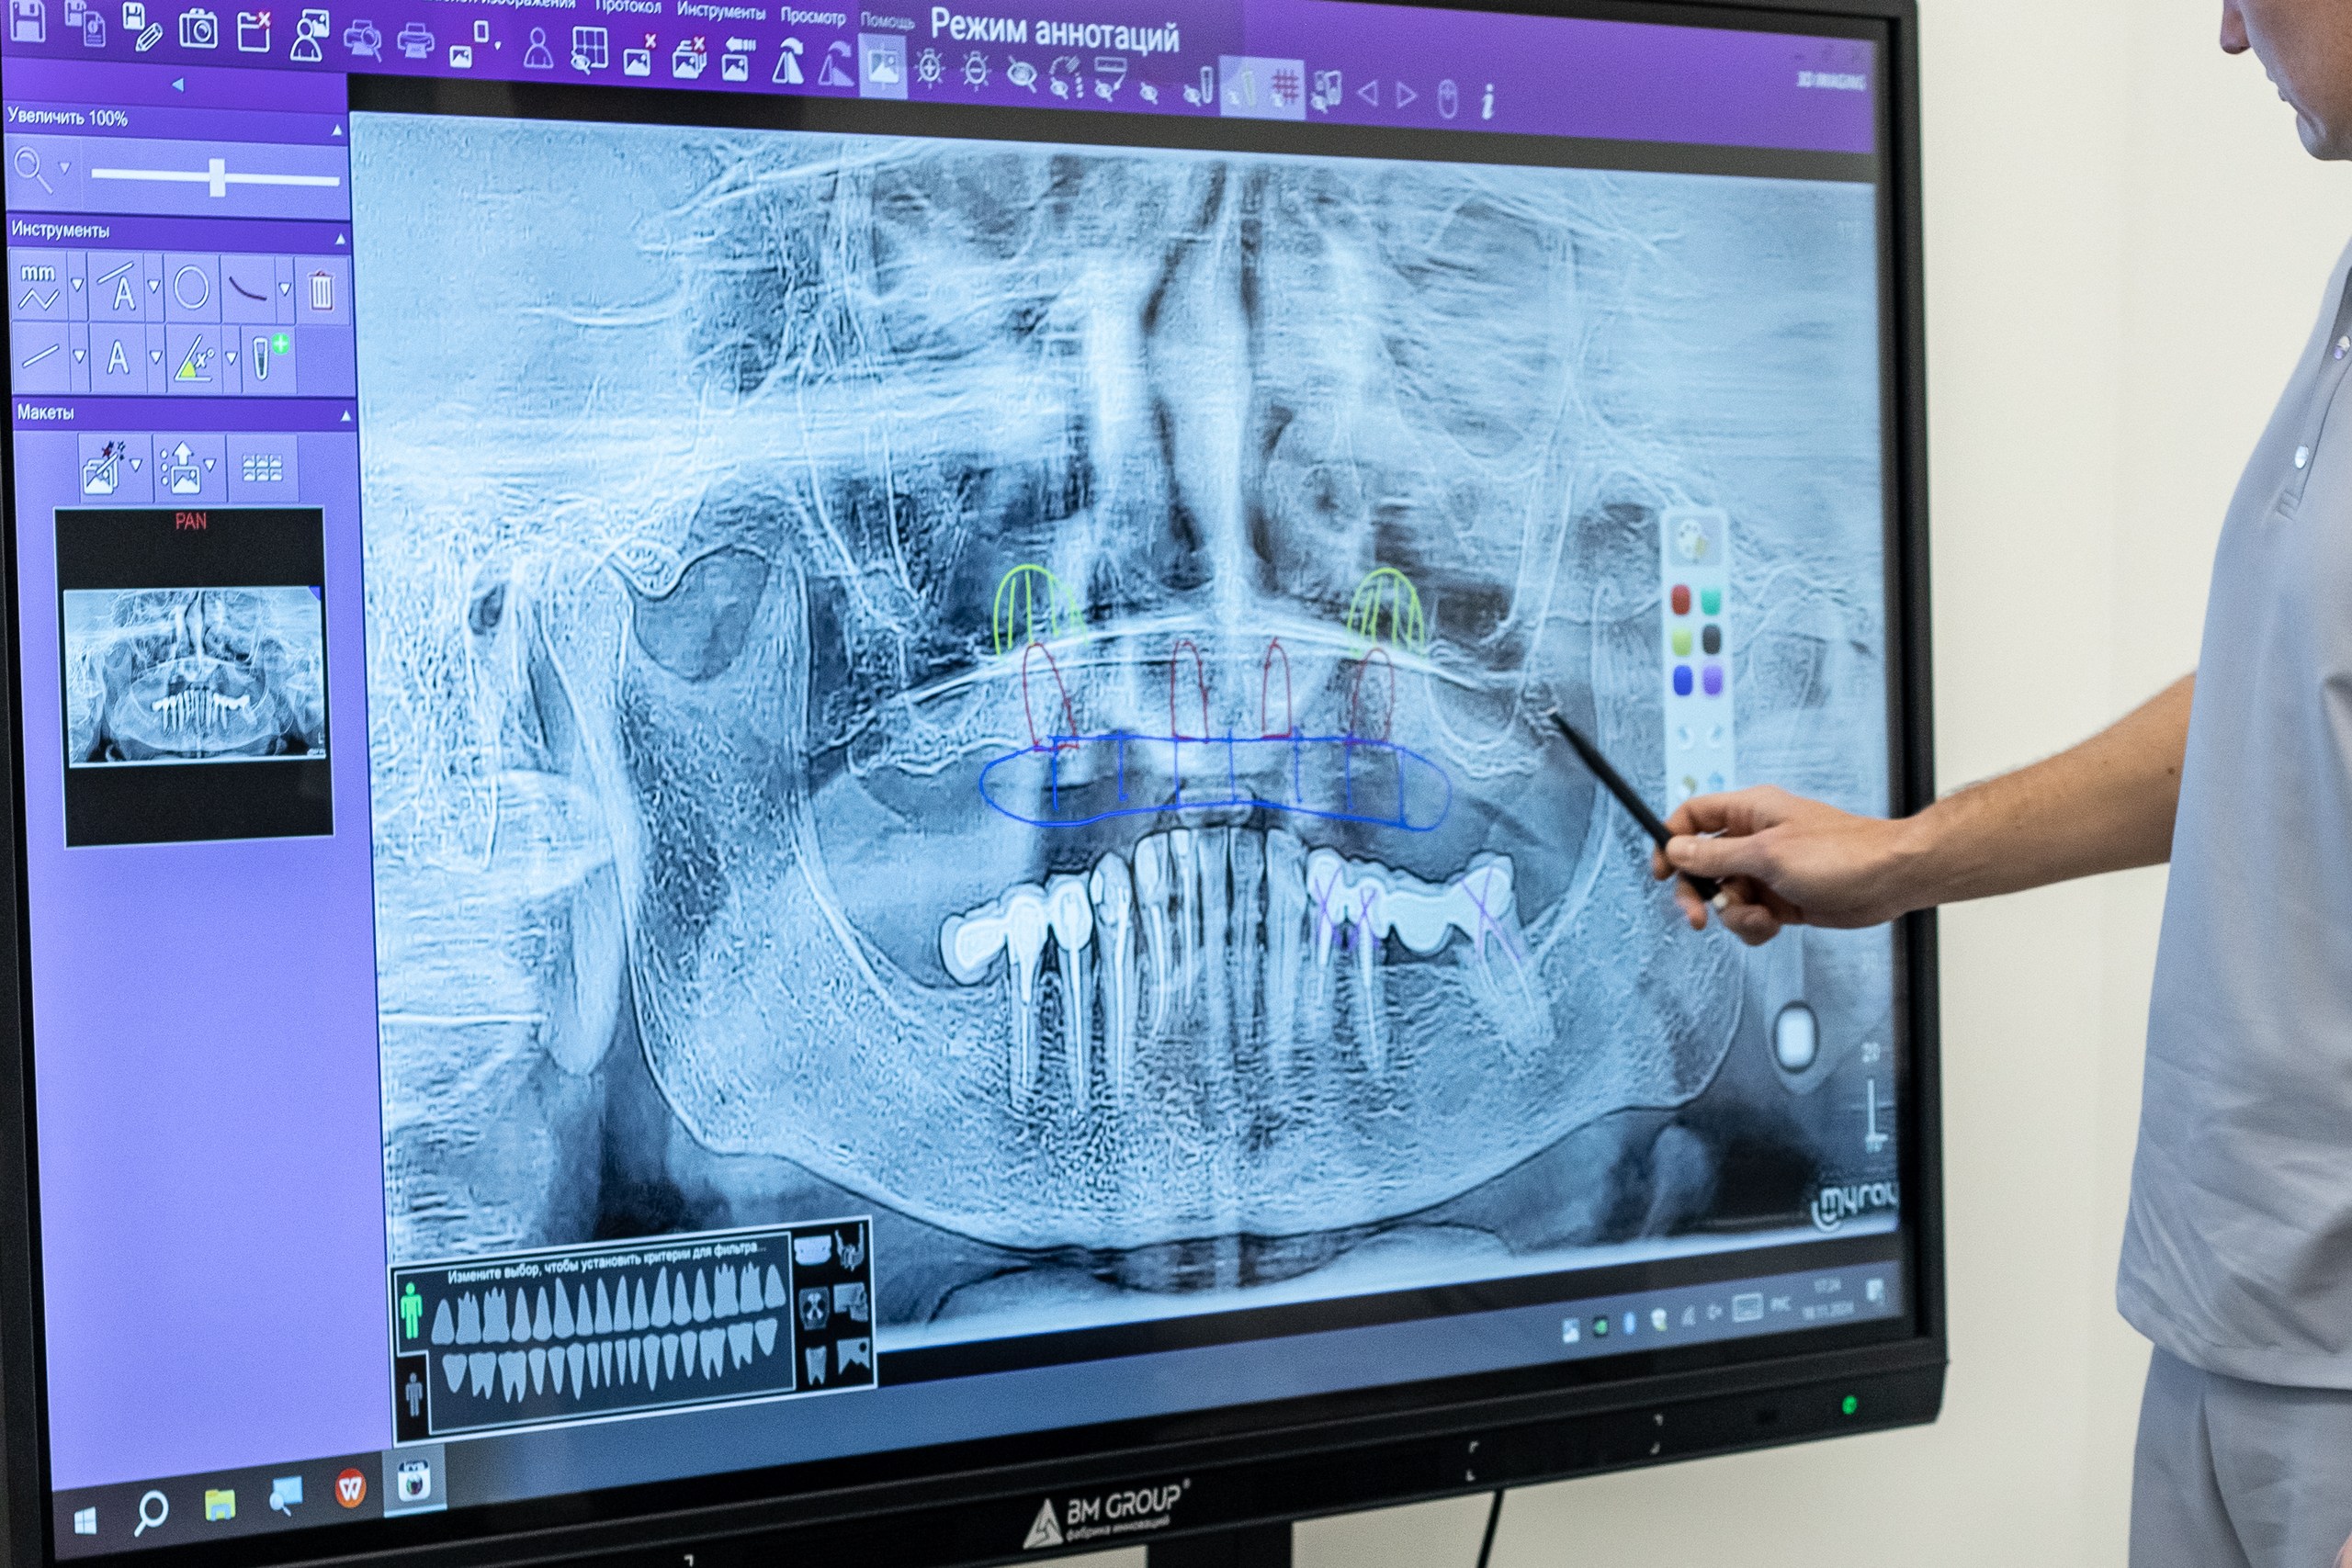

Итальянское оборудование OMS

Ультраточные снимки:

КТ и ОПТГ

КТ и ОПТГ

Новейший 3D-сканер для полного обследования

Самые современные подходы к лечению